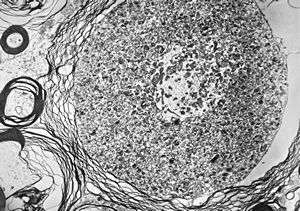

F,2y. | normal n. suralis